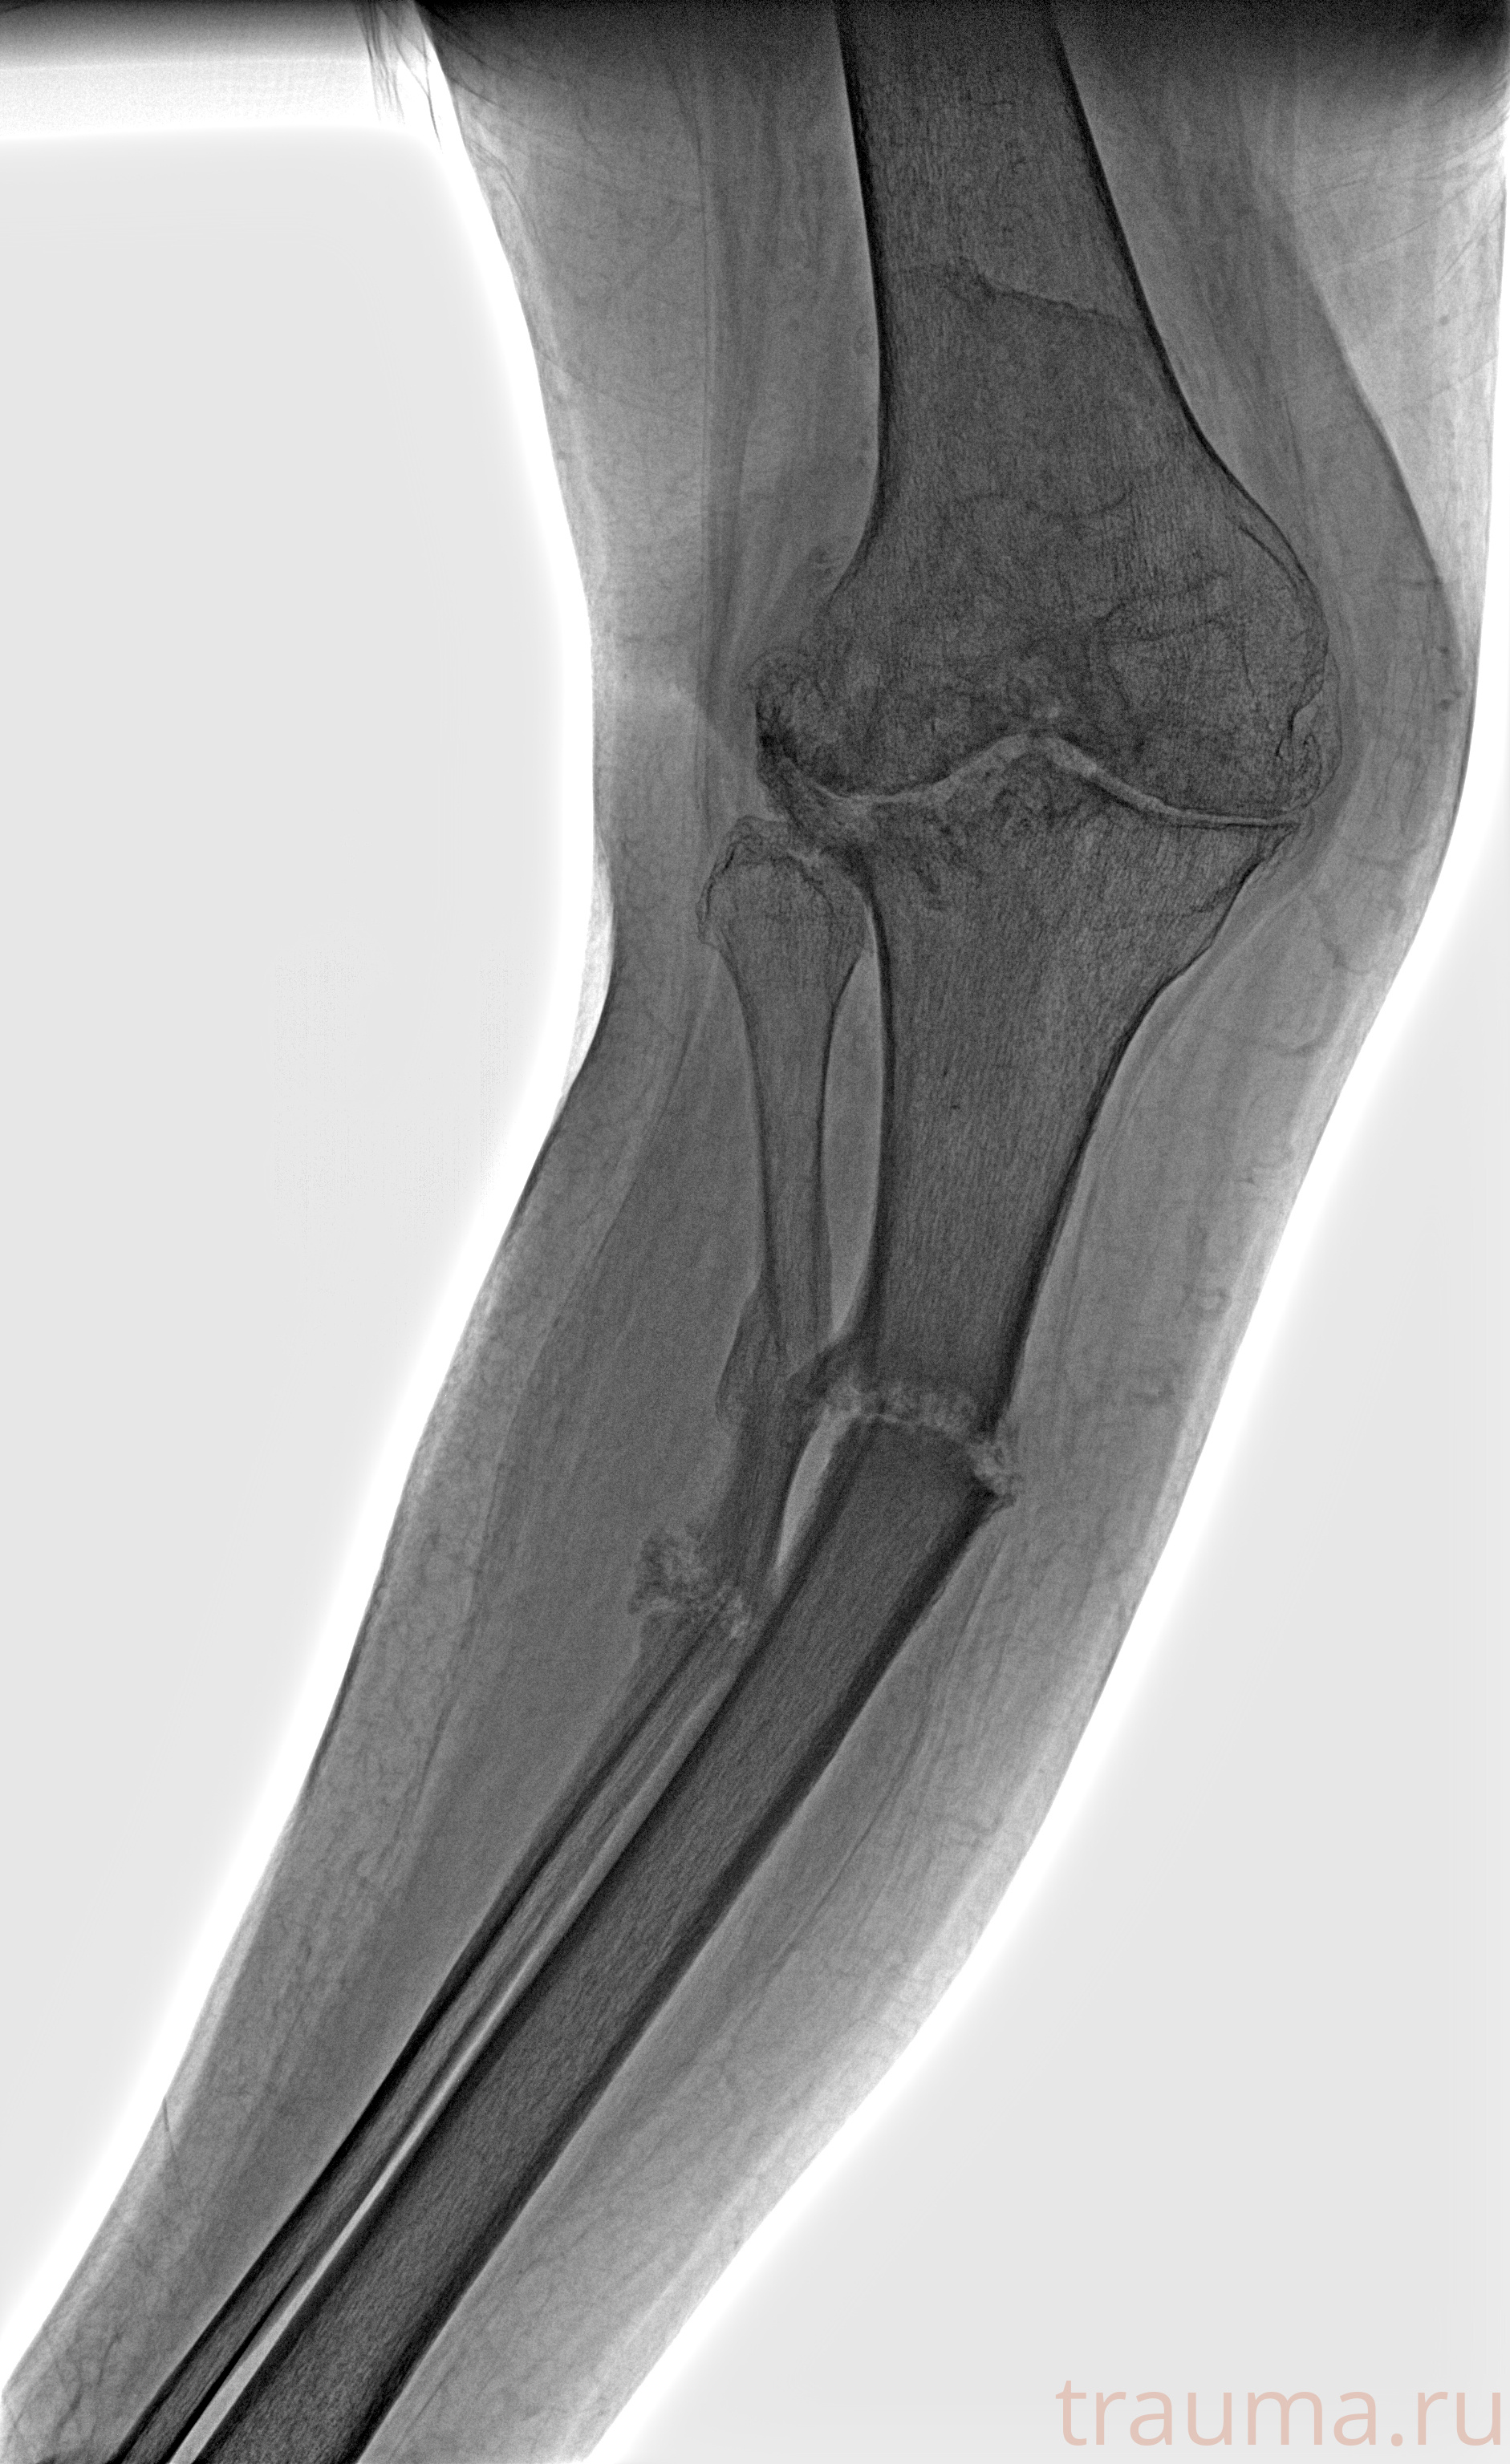

Рентгенограммы

Рентген на дому: по вашему адресу приезжает врач-рентгенолог, травматолог-ортопед с мобильным рентгеновским аппаратом, проводит диагностику травмы или заболевания, делает необходимые рентгенограммы, дает рекомендации по дальнейшему лечению. Получить качественные снимки в домашних условиях возможно благодаря уникальной методике, разработанной МосРентген Центром для института  Склифосовского